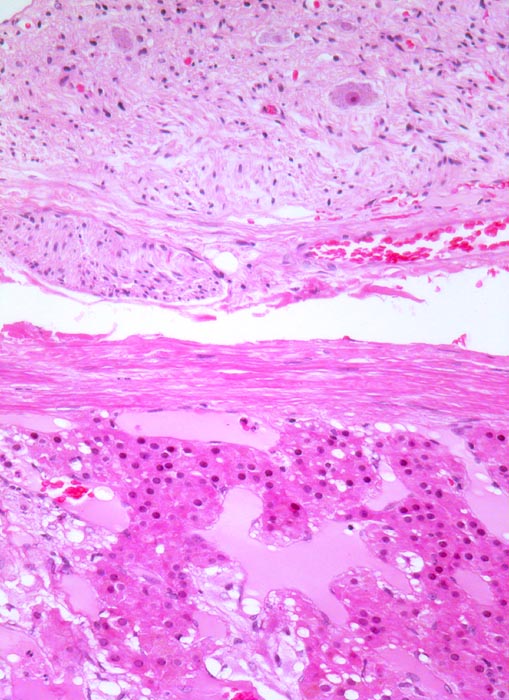

Phaeochromozytom

Nebenniere

Das Phaeochromozytom infiltriert die Nebennierenrinde. Die Nebenniere hat eine schmale bindegewebige Kapsel. Ganglion im periadrenalen Weichteilgewebe mit mehreren Ganglienzellen.

Der Patient klagt über rezidivierende Kopfschmerzen seit zirka zwei Monaten. In letzter Zeit hat er Alcacyl genommen, jedoch ohne Erfolg. Die Computertomographie des Abdomens zeigt einen 5cm grossen Tumor im Bereich der rechten Nebenniere. Die Familienanamnese für multiple endokrine Neoplasien (MEN) ist bland.

100